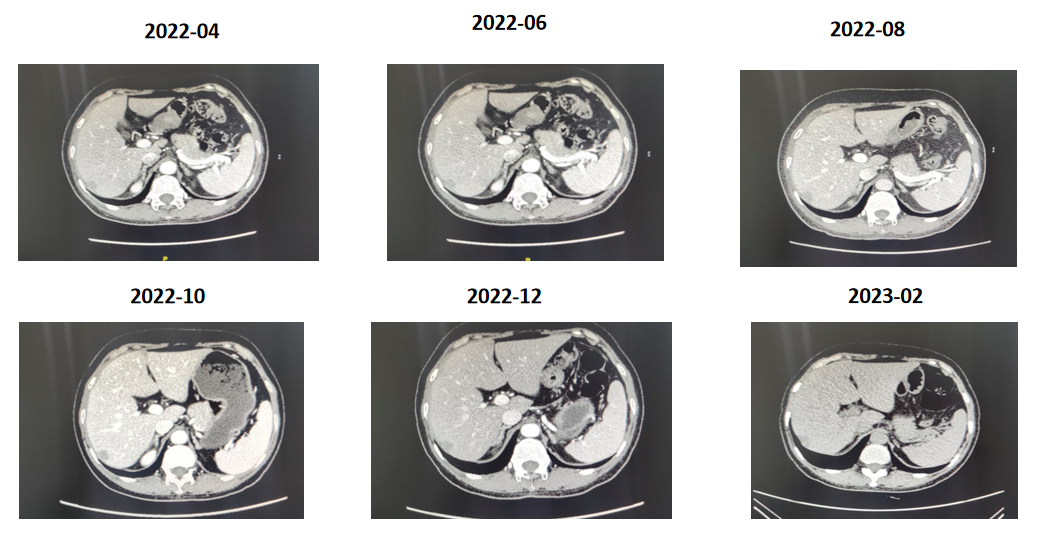

再次沟通后患者于2023-06-25起予德曲妥珠单抗300mg维持治疗,主要不良反应:轻度恶心,粒细胞减少,脱发,监测ILD。

疗效评估PR,PFS2=32m

患者目前仍在继续用药中,最后一次用药时间为2026年2月9日,截至目前PFS超32个月。

该患者最初术前影像学评估为T1N0M0,因此患者当时未接受穿刺,也未接受新辅助治疗,可能对后续预后存在一定影响。患者术后病理提示为局部晚期HER2阳性乳腺癌,术后辅助抗HER2曲帕双靶治疗结束11个月后出现肝转移,确认为原发耐药。二线使用吡咯替尼+卡培他滨取得14个月的PFS,验证了小分子TKI在耐药人群中的疗效。后续使用T-DXd治疗,再次获得深度缓解(PR),目前患者仍在继续用药中,PFS时间已经超过32个月,该患者的治疗过程充分体现了新一代ADC药物的强大实力,以及为HER2阳晚期患者带来持续的疾病缓解和生存获益。

回归本病例,当患者在接受吡咯替尼联合卡培他滨治疗14个月后再次出现进展,且出现肝、腹膜侵犯等更广泛的转移时,病情更为复杂。彼时,T-DXd在HER2阳性乳腺癌患者治疗中展现出了显著的优势,且T-DXd已在我国获批用于HER2阳性晚期乳腺癌患者的治疗。基于此强有力的循证依据和指南推荐,为该患者选用T-DXd是及时且正确的决策。患者在接受T-DXd治疗后,肝转移灶显著缩小,肿瘤标志物大幅下降,再次获得深度缓解(PR),目前患者仍在持续接受T-DXd治疗,PFS时间已经超过32个月,这一结果充分印证了T-DXd的强大抗肿瘤活性。在DB03研究亚组分析中可以看到,前线使用T-DXd治疗相比后线使用可延长无进展生存期(37.3 vs.23.9),提示更早使用T-DXd会更有效改善患者生存。同时,这也提示我们,若患者在二线治疗时能及时使用T-DXd,或许能够获得更早、更长的生存获益。随着T-DXd可及性的不断提升,相信未来将有更多患者能够在更早治疗阶段获益于该药物,实现长期高质量的生存。